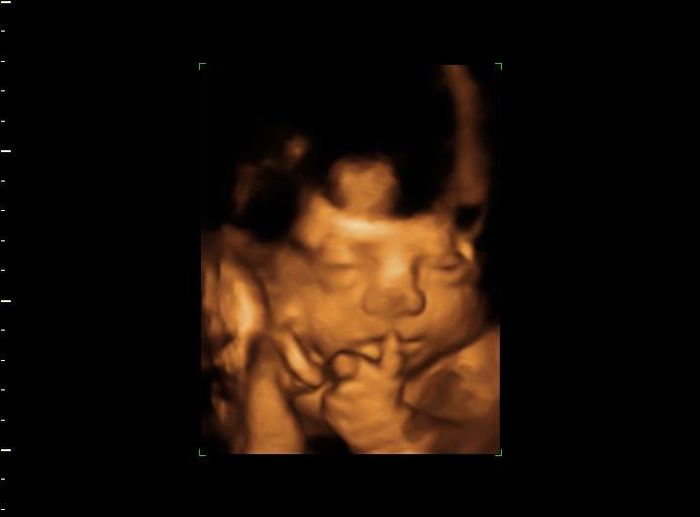

O Mês de Março tem um novo marco na nossa vida... Foi a 1 de Março de 2011 que a nossa historia começou... Passados 10 anos, a maior parte deles a viver à distância, a 14 de Março nasceu a prova do nosso amor: XAVIER Sempre tive a intuição que ele...

Adicionei uma foto no post de Sofia

Oi oi Noivinhas, casadas e mamas... É verdade, tenho andado desaparecida... mas finalmente arranjei um tempinho para vos contar as novidades... Da ultima vez que vos escrevi, tinha descoberto que estava gravida... um sonho de criança, pois sempre...